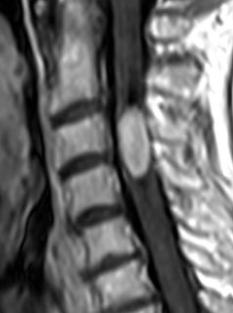

Ependymome Myxopapillaire

- Variante de l’Ependymome Spinal

- Départ du filum terminale (= intradural extra-médullaire)

- Lobulées, ovalaires, en saucisse

- Peuvent faire des syndromes de la queue de cheval

- Peuvent saigner (spots hémorragiques hypoT1, bordure d’hémosidérine)

de la colonne épendymome myxo papillaire